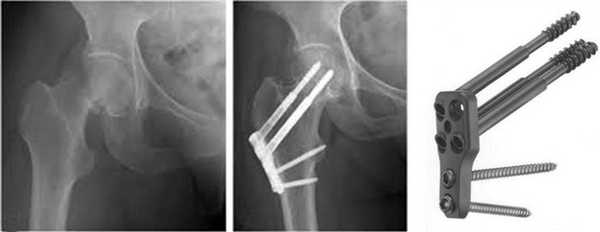

Остеосинтез ТБС на рентгене

Остеосинтез при переломе шейки

При ПШБ в основном проводится внутренний (погружной) остеосинтез. То есть, специальная фиксирующая конструкция соединяется непосредственно с костными структурами после оперативного обнажения места перелома. В ортопедии применяют два вида внутреннего соединения репонированных отломков:

- интрамедуллярный (внутрикостный);

- экстрамедуллярный (накостный).

Экстрамедуллярный способ

Экстрамедуллярная технология - это наложение пластин с шурупами, серкляжных швов из проволочного материала или колец на кость. Фиксирующий элемент будет располагаться вне костномозгового канала. Модели современных конструкций представлены разнообразным ассортиментом (Г-образные пластинки, пластины с трехлопастным гвоздем и др.). Накостного вида имплантаты, если речь не идет о проволочных швах и установке колец, по большей мере не требуют применения дополнительной внешней фиксации (гипсования) конечности.

Чтобы осуществить экстрамедуллярной пластинкой «связку», сначала обнажается пораженный сегмент. Затем фрагменты шейки выставляют в правильном положении, следя за точным соответствием примыкающих друг к другу концов. После примеряется пластинка, а дальше она укладывается сверху на кость и прижимается костодержателем. Через ее отверстия поочередно в кортикальный слой каждого фрагмента вкручивают винты. Ввинчивание резьбовой детали в конечную точку производится только после проведенной костной компрессии посредством специального приспособления.